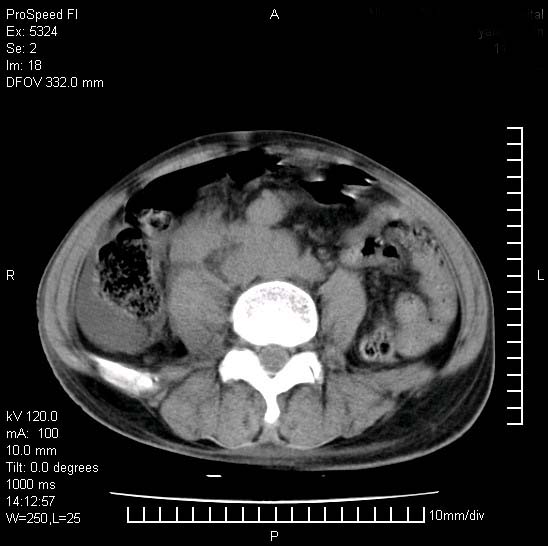

患者阴囊肿大14月,腰痛2个月,咳嗽,咳痰1周,患者现在肾功异常,做增强有些担心,我们用的是欧乃派克.

右侧肾癌伴腹膜后淋巴结转移!

右侧肾癌后腹膜转移,腹腔少量积液

腹膜后淋巴结肿大包饶腔静脉,双肾病变,建议增强

双肾均有软组织密度舯物,腹膜后淋巴结肿大包饶腔静脉------考虑为恶性占位病变,转移瘤可能。

左肾也有问题呀///

支持:双肾均见软组织密度肿块影,腹膜后淋巴结肿大包绕腔静脉------考虑为恶性占位病变,转移瘤可能。

1)考虑双肾恶性肿瘤(肾癌?)。2)腹膜后淋巴结肿大,多为肿瘤转移所致。

腹腔积液,双肾均有稍高密度肿块,主动脉旁广泛淋巴结肿大,融合,无显著肿块坏死征像,多考虑淋巴瘤累及双肾,不排除肾癌伴转移(肾癌这么大应该较多坏死了),另阴囊肿大,不知是实质肿大还是阴囊积液,如是是积液,多为腹腔肿块压近睾丸静脉所致,如是是实性的,多为淋巴瘤

1、淋巴瘤,双肾转移瘤;2、双侧肾癌,伴有腹膜后淋巴结转移。

双肾周围及腹膜后改变符合恶性病变,现在关键是要明确阴囊肿大的原因,是否为肿瘤性病变.如阴囊为恶性肿瘤那一切用转移即可解释,如阴囊为水肿改变,那需重新分析检查明确.

双肾均有软组织肿块伴腹膜后淋巴结肿大融合,右侧结肠旁沟积液;考虑恶性肿瘤。转移瘤?淋巴瘤?

阴囊肿大是实质性的么,为什么不扫阴囊,此扫描做的是什么部位,肾脏没包括全,也可以考虑生殖系统肿瘤转移

双肾增大,腹膜后多发肿大淋巴结影.首先考虑淋巴瘤.

双肾增大,结合腹膜后淋巴结肿大,考虑双肾恶性肿瘤并转移可能。

双肾癌并腹膜后淋巴结转移

考虑恶性淋巴瘤侵及双肾,腹膜后淋巴结肿大。